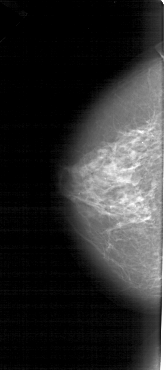

A_1277_1.LEFT_MLO

LEFT_MLO LINES 5446 PIXELS_PER_LINE 2536 BITS_PER_PIXEL 12 RESOLUTION 43.5 NON_OVERLAY